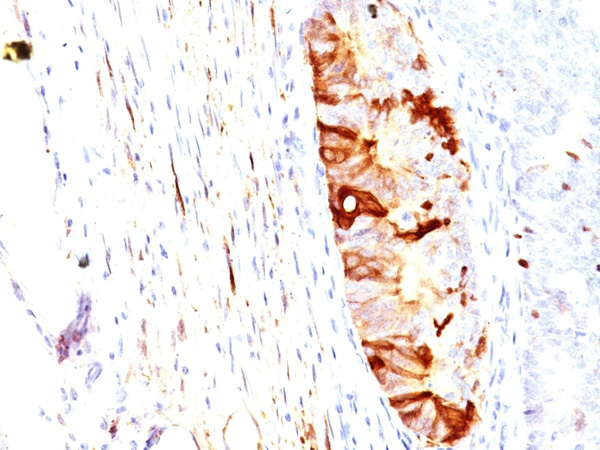

(Formalin-fixed, paraffin-embedded human Colon Carcinoma stained with ALDH1A1 Mouse Monoclonal Antibody (ALDH1A1/1382).)